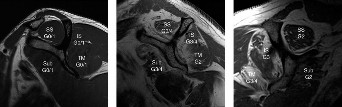

In addition, Goutallier et al. formulated a classification system for rotator cuff tears that is helpful in determining whether a massive rotator cuff tear is reparable or not based on fatty degeneration. Progressive atrophy and fatty degeneration occurs as the length of time the rotator cuff has been torn increases. The fat to muscle ratio is used in the Goutallier classification. The cause of this atrophy and degeneration is not fully understood but is likely due to a combination of loss of mechanical tension of the muscle and muscle denervation.

This classification was originally based on CT imaging but is now applied to MRI imaging and uses sagittal oblique views at the most lateral slice in which the scapular spine is continuous with the scapular body. There are five categories that range from stage 0 to stage 4. A classification of stage 0 is normal, stage 1 is some fatty streaks, stage 2 is more muscle than fat, stage 3 is equal amounts of fat and muscle, and stage 4 is more fat than muscle. This patient’s rotator cuff tear involves the supraspinatus and infraspinatus, and both have atrophied to the point of having equal amounts of fat and muscle, giving her tear a Goutallier classification of stage 3 (see Table 2–2 and Fig. 2–18). As a general rule, if there is stage 3 or 4 fatty atrophy, rotator cuff repair will not be successful and a reverse total shoulder or tendon transfer would be a better operation.

Figure 2–18_Three different patients showing different stages of fatty degeneration with Goutallier stages. Higher stages are predictive of worse outcomes after rotator cuff repair. SS, supraspinatus; IS, infraspinatus; TM, teres minor; Sub, subscapularis. (From Kuzel BR, Grindel S, Papandrea R, Ziegler D. Fatty infiltration and rotator cuff atrophy. _J Am Acad Orthop Surg. 2013;21(10):613–623.)